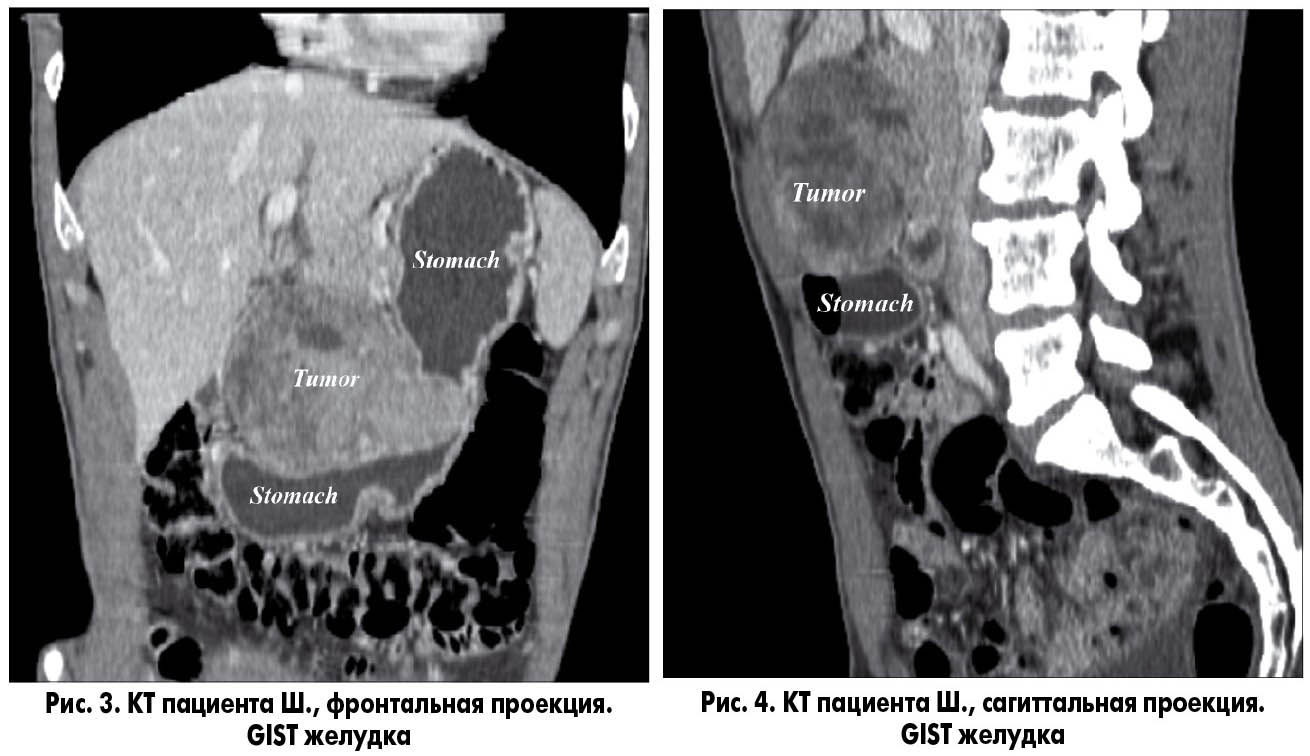

| Компьютерная томография (КТ) | Высокоточное изображение внутренних структур с помощью рентгеновских лучей․ | Обнаружение даже мельчайших образований и metastatических очагов․ |